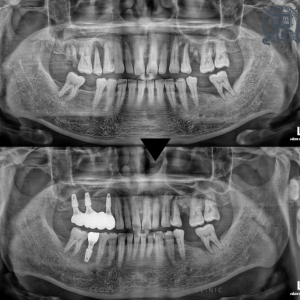

광복동치과, 소홀했던 치주질환 임플란트로 기능회복! 안녕하세요. 광복동치과 서울화이트S치과 입니다. 최근 몇 년동안 19세 이상 성인의 병원 외래 질환에서 치주질환이 1,2위를 차지할 만큼 치주질환으로 불편함을 호소하시는 분들이 많이 계십니다.…